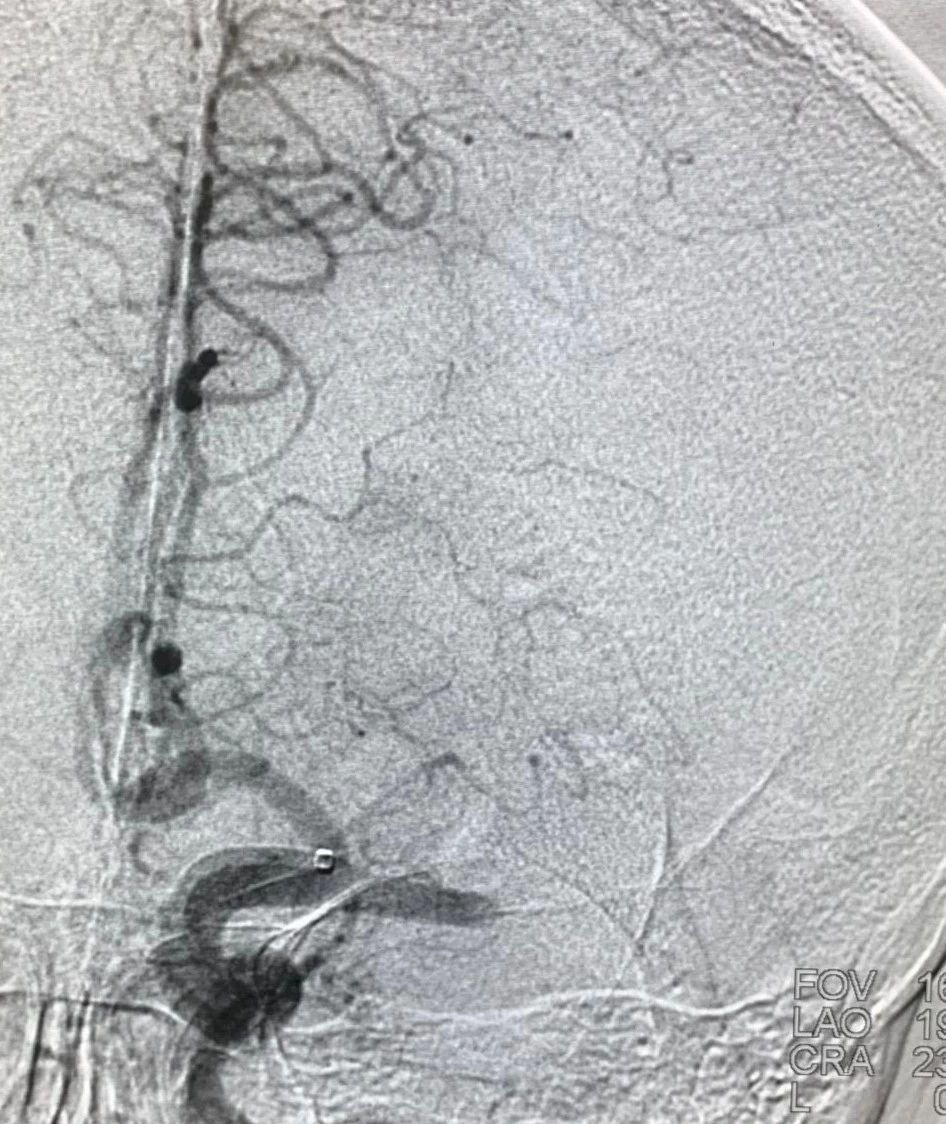

8F Envoy 90cm 强生公司

5F Navien 125cm 中间导管 美敦力

TJMC 16 微导管 (泰杰伟业)

Synchro2 200cm 微导丝 史赛克

通过推拉按摩技术后支架打开好转。

术后造影,mTICI分级III。